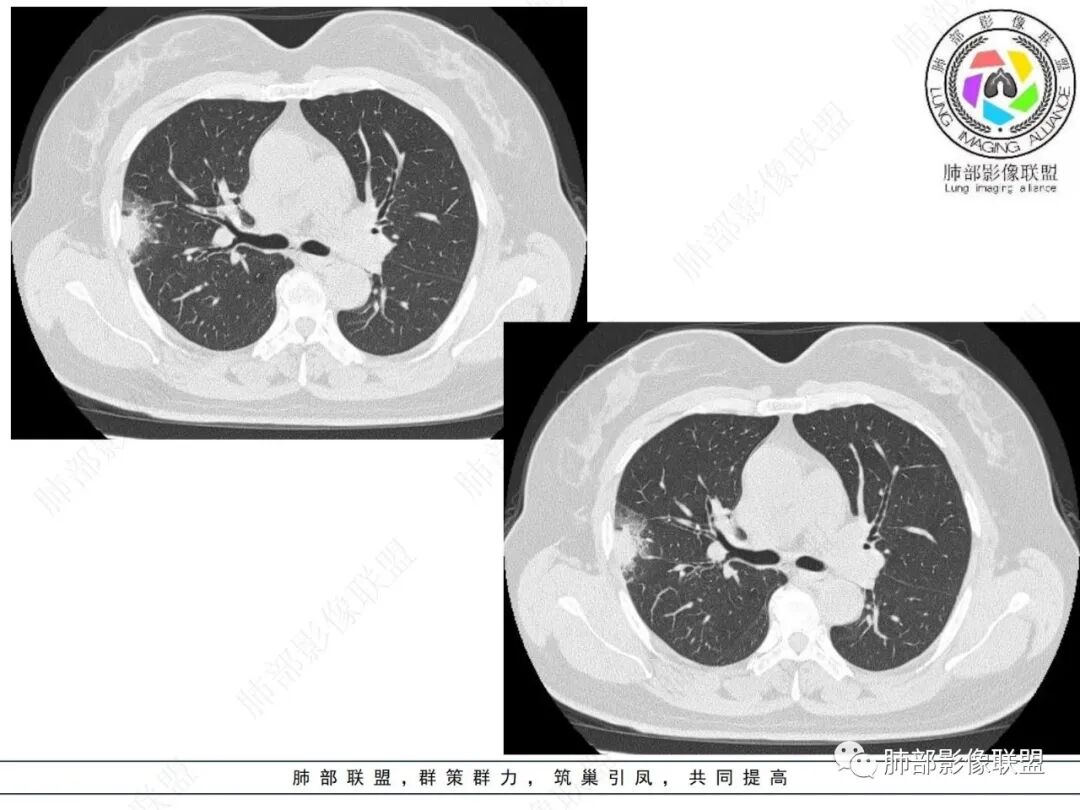

2.影像特点:

右肺上叶胸膜下混合磨玻璃团片影。

周围磨玻璃部分间杂条索状高密度区,密度欠均匀(可疑重力分布趋势),其磨玻璃影边界大多较清楚或可分辨,部分“L型”边缘,提示小叶间隔阻挡可能。血管穿行自如,可疑远端支气管进入。

实性部分较密实,不规则,隐约见棘突或刺状突起,未见钙化、空洞或液化区,实性边缘可见斑状略低密度间隙(借用王兆宇老师课件,称其呈“松软”的形态)。动脉期实性部分较明显不均匀强化,如果有完整增强图,还可以观察内部血管情况。

纵隔窗相对肺窗病灶相对小,仅部分实性影呈现。病灶张力不高,相邻胸膜增厚(糊墙),未见明显胸膜牵拉凹陷。

未见卫星病灶,远处未见磨玻璃结节影。

双肺门及纵隔未见明显增大淋巴结。心包及胸腔未见积液。